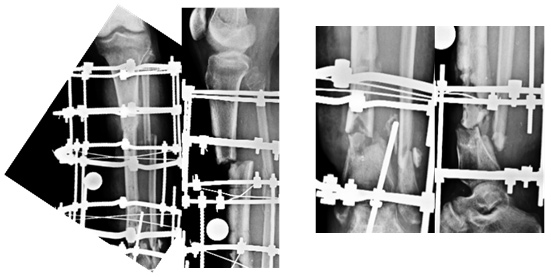

X-rays at Presentation

The x-rays showed nonunion at both the upper and lower fracture sites. The lower fracture site showed infection and dead bone. The fixator was not holding the bone fragments in good alignment and the wires were all loose and some of them were infected.